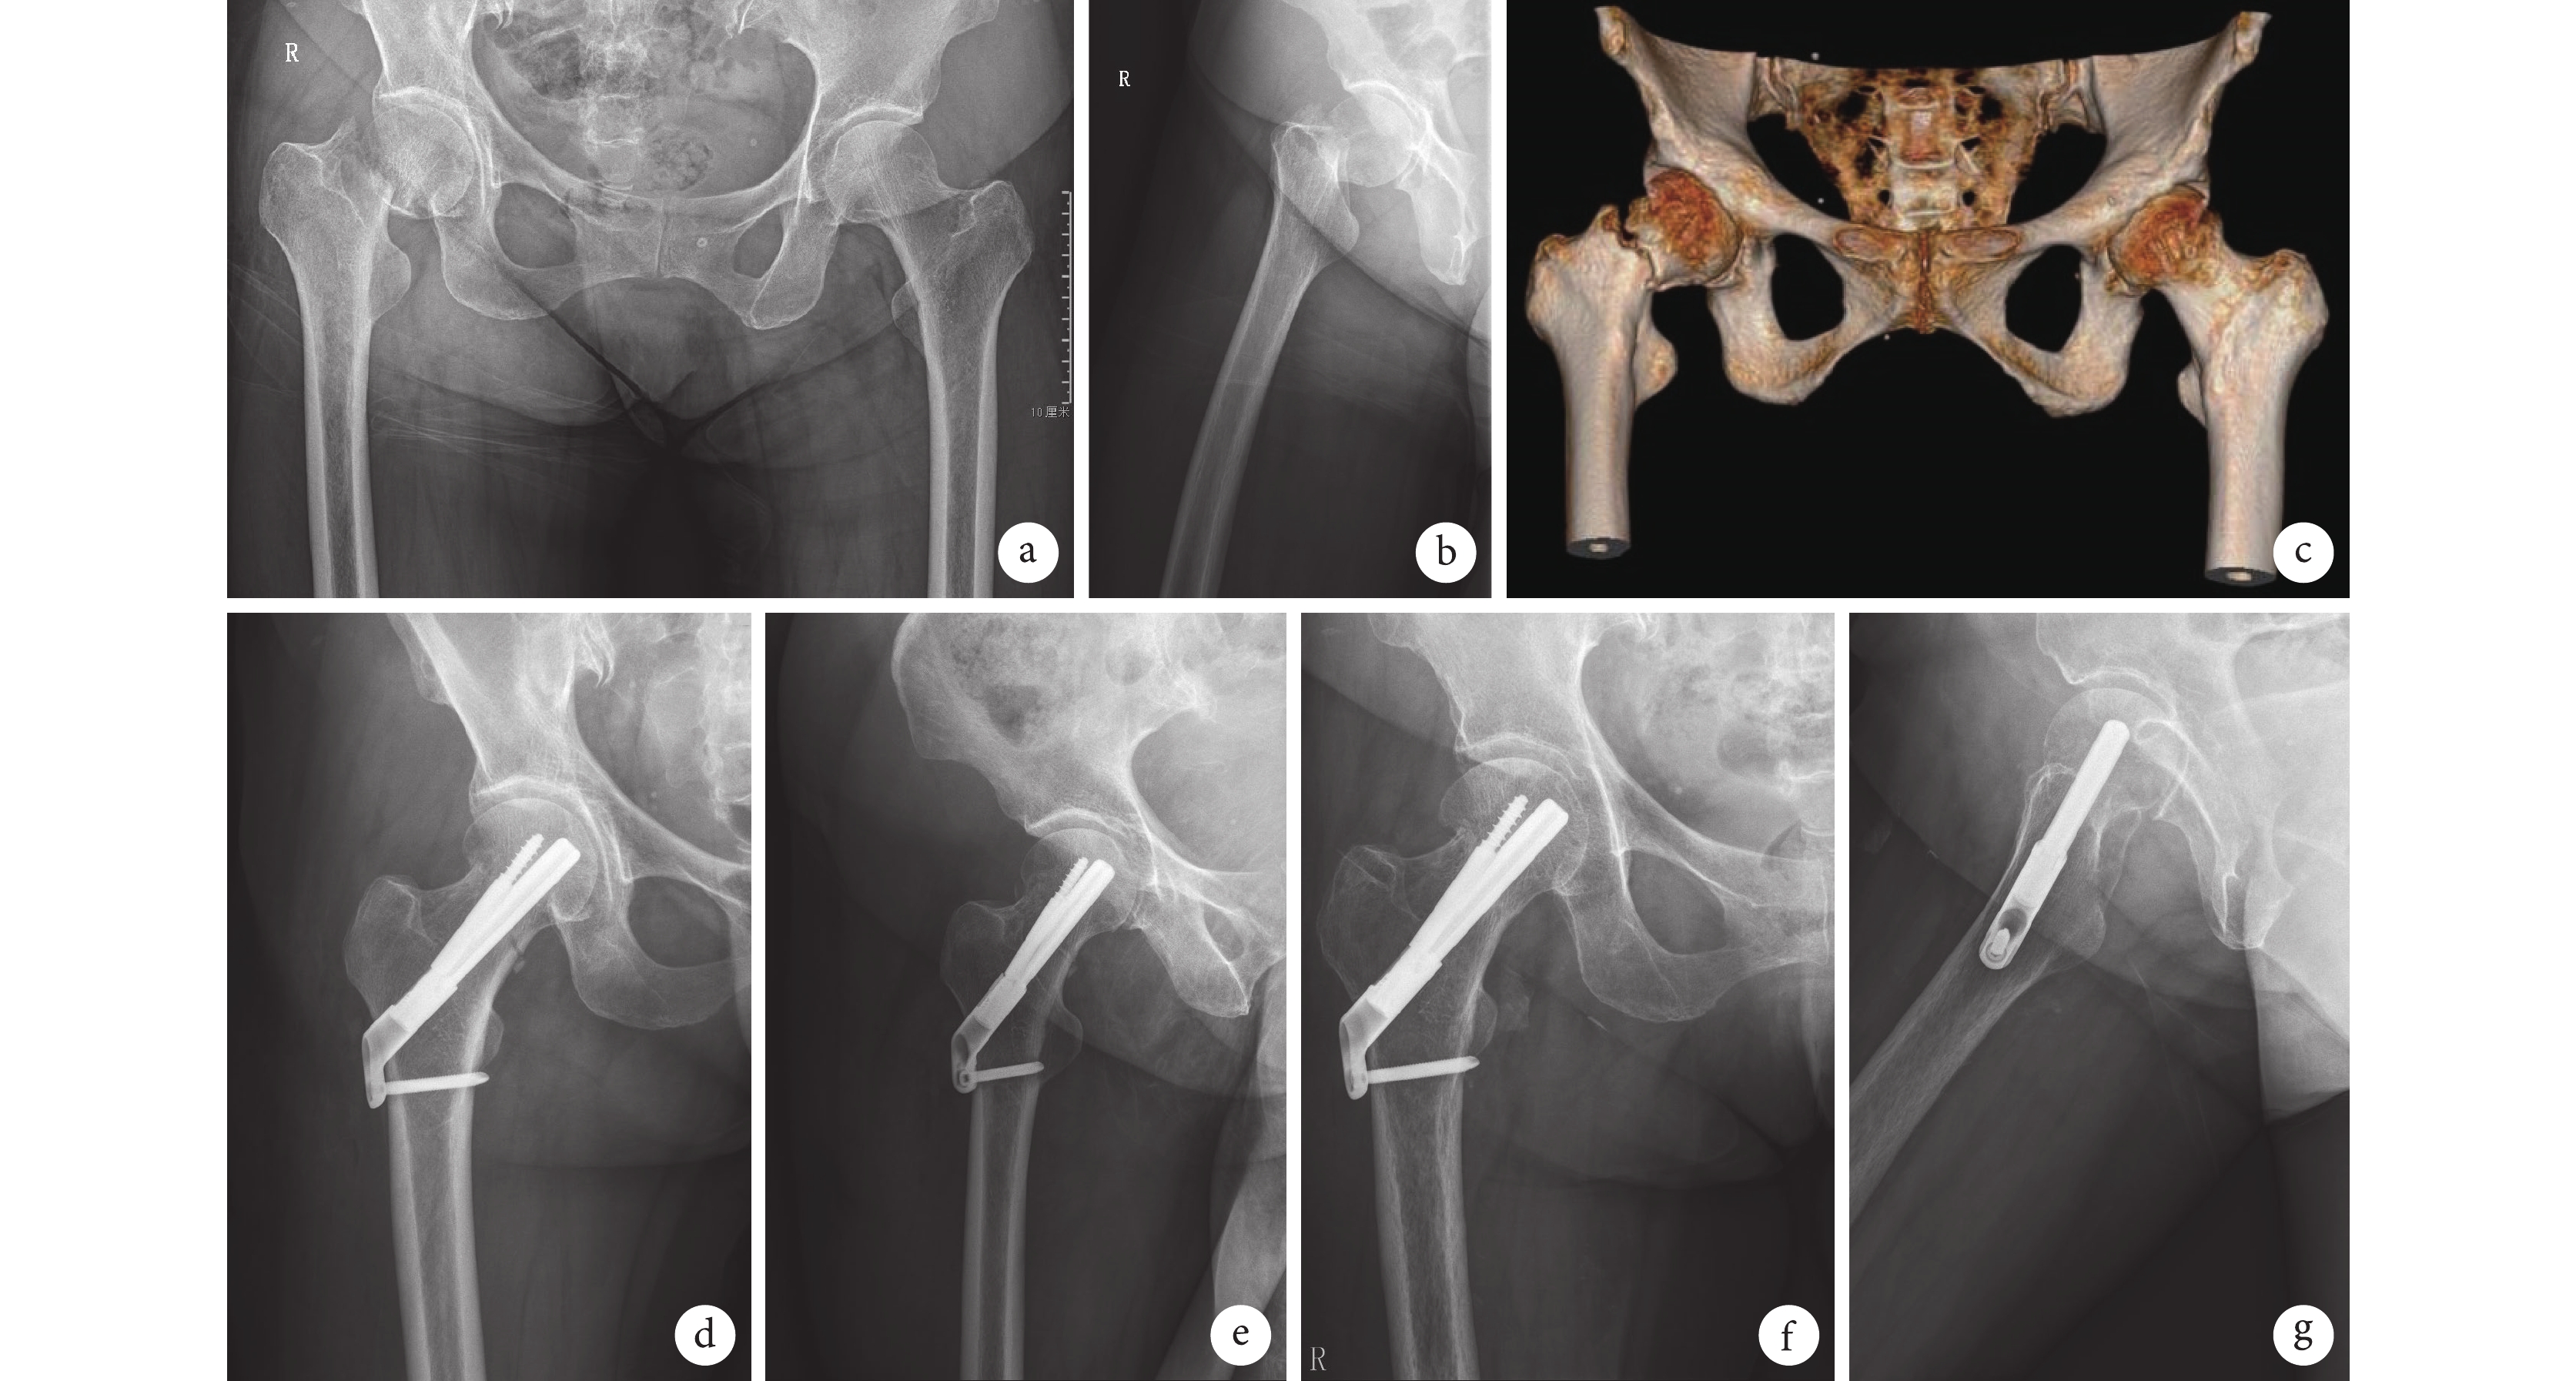

術后兩組患者均獲隨訪,隨訪時間4~16個月,平均7個月。試驗組1例術中切開復位者骨折不愈合,股骨頸短縮>1 cm,末次隨訪時尚未出現螺釘切出,未作特殊處理,進一步隨訪中;其余患者骨折均愈合。試驗組及對照組骨折愈合時間分別為(17.6±1.9)、(18.2±1.9)周,組間比較差異無統計學意義(t=0.957,P=0.345)。末次隨訪時,試驗組Harris評分為(82.4±5.8)分,高于對照組(79.0±7.7)分,但差異無統計學意義(t=?1.483,P=0.147)。見圖2。

a~c. 術前正側位X線片及CT三維重建; d、e. 術后1 d正側位X線片;f、g. 術后7個月正側位X線片示骨折愈合

Figure2. A 57-year-old female patient with right femoral neck fracture (Garden type Ⅲ, Pauwels type Ⅲ) in the trial groupa-c. Anteroposterior and lateral X-ray films and three-dimensional CT before operation; d, e. Anteroposterior and lateral X-ray films at 1 day after operation; f, g. Anteroposterior and lateral X-ray films showed the fracture healing at 7 months after operation